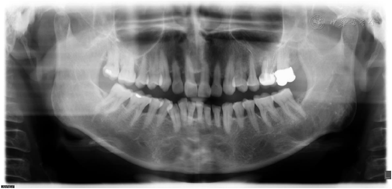

全口临床检查:口腔卫生状况一般,菌斑、软垢少量,下前牙舌侧可见新生牙石,龈下牙石(++)。牙龈色偏红,肿胀,形态圆钝,质软,尤以下前牙舌侧为重,出血指数3~4。全口牙齿探诊深度(PD)5~7 mm,个别位点8~9 mm。全口牙齿均可探及附着丧失,21、24、25、41、43松动I~Ⅱ。46合面金属色充填体,27烤瓷冠复体,近中悬突,可见食物嵌塞,叩痛(-)。咬合关系深覆合,下前牙多生牙,下前牙区拥挤,43位置颊倾,反合,见图1,图2,图3。

全口影像学检查:12~22、25~26、34~36、45~46牙槽骨吸收进一步加重,但下颌出现骨白线,26远中冠部低密度影像近髓腔,根尖周无低密度影像。

12年后复查时,口腔卫生状况良好,牙龈色偏粉,全口探诊4~6 mm,后牙区个别位点7~9 mm,探诊出血阳性率(89.3%比55.3%)和PD≥5 mm(38.6%比24.4%)百分比均下降,全景片显示牙槽嵴顶骨白线清晰、连续。

完善的牙周基础治疗可以控制绝大多数的牙周炎症,在重度牙周炎的病例中,也可获得良好的治疗效果[5,6]。本病例中经过12年的治疗,影像学显示牙周状况稳定,但对于后牙区垂直型骨吸收应尽早进行牙周手术治疗;另一方面考虑26烤瓷冠对邻面骨吸收的影响。

本病例中患者在经过1轮完善的牙周基础治疗后症状明显改善,自此于外院门诊行长达7年的洁治术。与7年前相比,可见牙槽骨有明显的降低。之后每年定期进行牙周维护治疗,可见牙槽骨硬骨板出现,连续。

该病例历经12年的牙周随访治疗,影像学显示牙槽骨维持稳定,患者16、26、36、46仍可探及深牙周袋,与患者反复沟通后,考虑行引导组织再生术以期获得牙周组织再生。